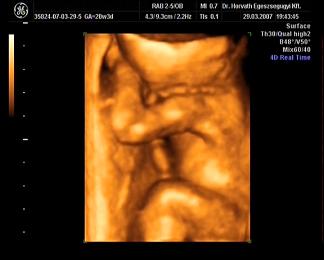

Mi meg megjöttünk az uh-ról, Ákosom nagyon szégyenlősvolt, már ami a kis arcát illeti, mert végig az arca előtt volt mindkétkeze, dörzsölte a szemét....néha profilból el lehetett kapni egy-egy pillanatot, szerintem gyönyörű...már olyan babás! Bezzeg a kukacát, azt mutogatta szorgosan! Meg megmutatta a kezeit, lábait, és hát néha a kis arcát is ki lehetett venni, de szemből teljesen most nem mutatta meg magát. De ami a legfontosabb, minden a legnagyobb rendben Vele, a gerince gyönyörű, gyomortelítődés szépen látható, vesék is szépek, koponya rendben....szóval minden okés, és ez a lényeg. Már 31O gramm a kis Drágám! Nagyon jó volt az egészvizsgálat, csak azt sajnálom, hogy nem sikerült képet készíteni Róla, pedig a doki mindent megtett...deDVD-t kaptunk, majd abból megpróbálok valamit kiügyeskedtetni Apával.

Bocsi, hogy ennyit raktam, de nem bírtam megállni :oops: :oops: :oops: